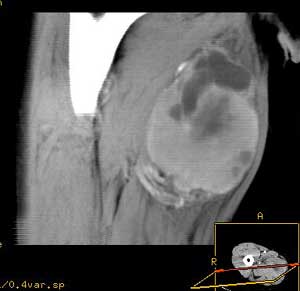

腺泡狀軟組織肉瘤--影像學檢查2、MRI檢查;

X線示左股部軟組織富血供性占位。鏡下所見:腫瘤細胞呈腺泡樣巢狀排列,瘤細胞大小不等,巢內緣不整,外周較圓滑,巢與巢之間為豐富的、互相連通的血管網。瘤細胞圓形、卵圓形或多角形,界清,胞漿豐富,有嗜酸性顆粒,核圓形,異型性小,含有核仁,核分裂象不易找到。